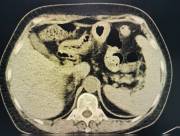

近日,西咸院区移植泌尿外科李智斌团队成功为一名复杂肾病患者同期实施“多囊肾切除+肾上腺肿瘤切除+肾移植术”。此次多术式联合手术,一次性解决了患者终末期肾病、巨大多囊肾及右侧肾上腺肿瘤三大难题,标志着三级片

在复杂器官移植领域取得了重要的突破。

该患者病情复杂,巨型多囊肾已对周围脏器造成严重压迫,同时肾上腺肿瘤导致原发性醛固酮增多症需长期口服药物治疗,而异体肾移植更是对手术精度和围术期管理有着极高要求。

手术过程中,李智斌带领团队沉着应对,精准解剖,在切除右侧巨型多囊肾和病变肾上腺之后,快速完成血管吻合,确保移植肾即刻恢复血流。整个手术历时近5小时,术后未出现并发症,现已转入普通病房康复。